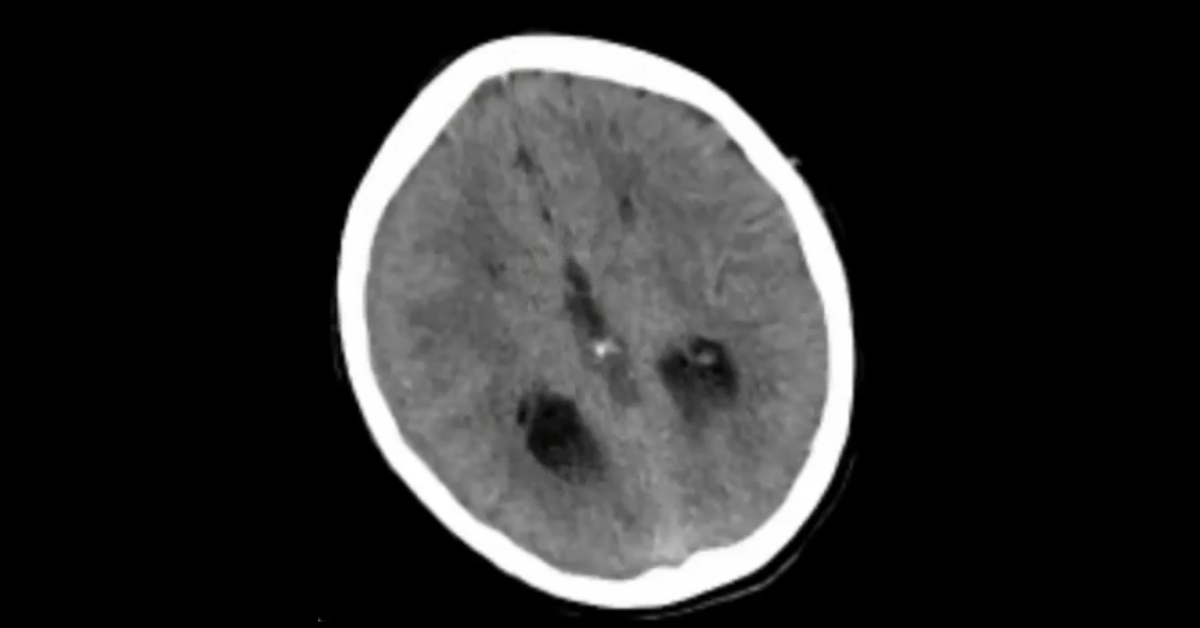

A collection of pediatric imaging cases highlighting a number of important pediatric pathologies.

1. Understand the implications of skull and rib fractures in the diagnosis of abusive trauma.

2. Appreciate the importance of multiplanar imaging in the diagnosis of skull fracture.

3. Learn the important anatomic structures to identify in evaluation of congenital brain abnormalities.